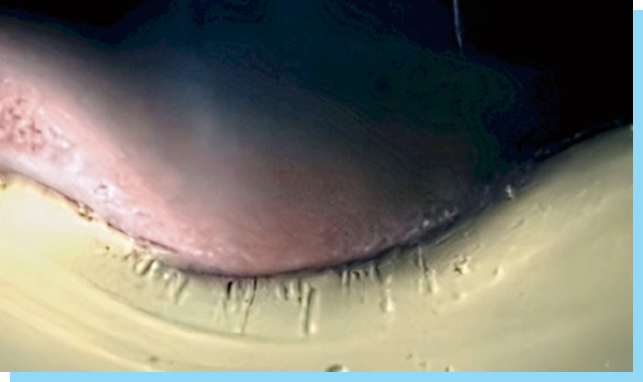

STEP 2

혈관 및 조직 수축으로

혈관 및 조직 수축으로

출혈, 멍, 붓기감소

-

-

[ 칠리프팅 후 거의 보이지 않는 자국 ]